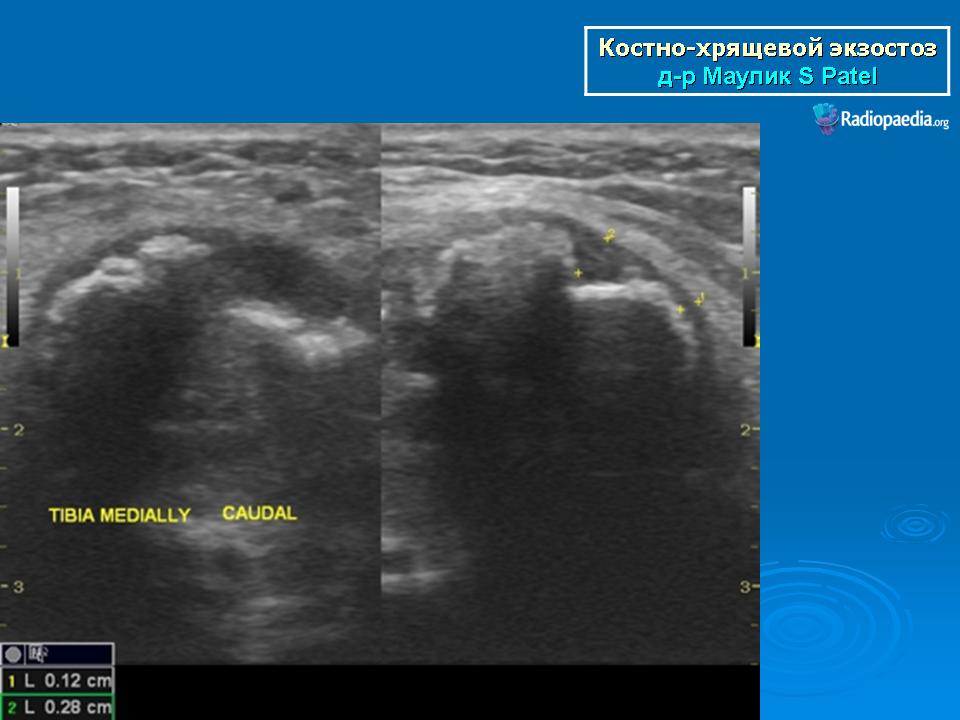

Локализация остеохондромы: частота поражения отдельных костей различна; нижний коней бедренной кости, верхние отделы плечевой и большеберцовой костей поражаются более чем у половины больных. На всем протяжении остеохондрома покрыта надкостницей. Она может быть обнаружена и в других костях, за исключением костей лицевого черепа. Все же поражение костей позвоночника, кистей рук и стоп встречается редко. При рентгенологическом исследовании видна типичная картина узкого или широкого выроста вблизи эпифизарной части пораженной кости. Обычно плотность узла неоднородная, имеются многочисленные плотные участки, соответствующие обызвествленным хрящевым долькам. Хрящевая «шапочка» большей частью не определяется, поскольку хрящ остается необызвествленным. Она может быть выявлена только при магнитно-резонансной томографии.